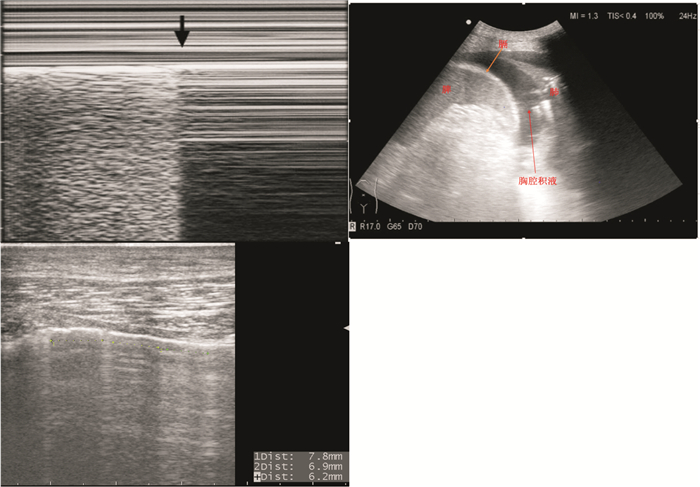

图 3 剑突下心脏切面

(2) tension pneumothorax (张力性气胸)。探查双侧上下blue点[13](图 4),明确胸膜滑动征、沙滩征、A线、B线等的存在与否,如上述征象消失出现平流层征或发现肺点 (图 5),考虑张力性气胸引起的梗阻性休克。但是在临床应用时应注意,对于张力性气胸的床旁超声筛查,应建立在临床症状、体征、病史的综合分析后,再进行相应的探查。如临床不支持张力性气胸表现,则可于肺部探查 (3P) 部分进行气胸鉴别诊断。

图 4 上、下blue点和膈点

图 5 肺点,胸腔积液,B线

2.4 3P原则 (评估肺脏,表 3) 2.4.1 pneumothorax (气胸)

探查双侧blue点 (图 4~5),明确胸膜滑动征、沙滩征、A线、B线等存在与否,如上述征象消失,出现平流层征或发现肺点,考虑气胸,结合其他部位超声探查,判断是否为梗阻性休克。

探查双侧blue点及膈点 (图 5),判断有无肺水肿;明确是否存在增多的B线,呈现肺火箭征。结合病史及前述的心脏评估,明确是否为心脏功能衰竭导致肺水肿。

2.4.3 pleura effusion (胸腔积液)

探查双侧膈点 (图 5),判断有无胸腔大量液性暗区,有无影响血流动力学的大量胸腔积液、积血等引起的休克。